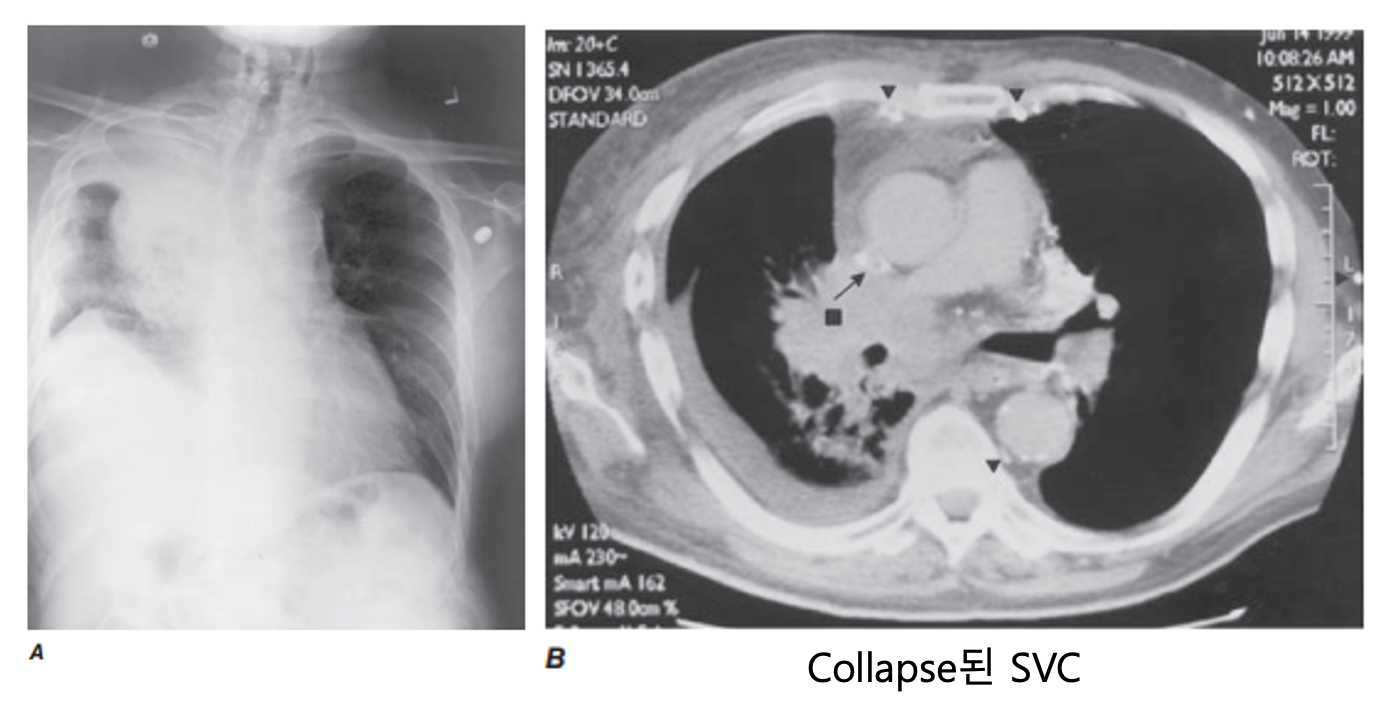

상대정맥 증후군

• 원인: 우측 폐 상엽 종양에 의한 외부 압박 (80-90%)

• 소세포폐암 (SCLC), 림프종 (Lymphoma)

• 기타: 혈전 (thrombosis)

• 진단:

• 조영 증강 흉부 CT (원인 및 압박 부위 확인)